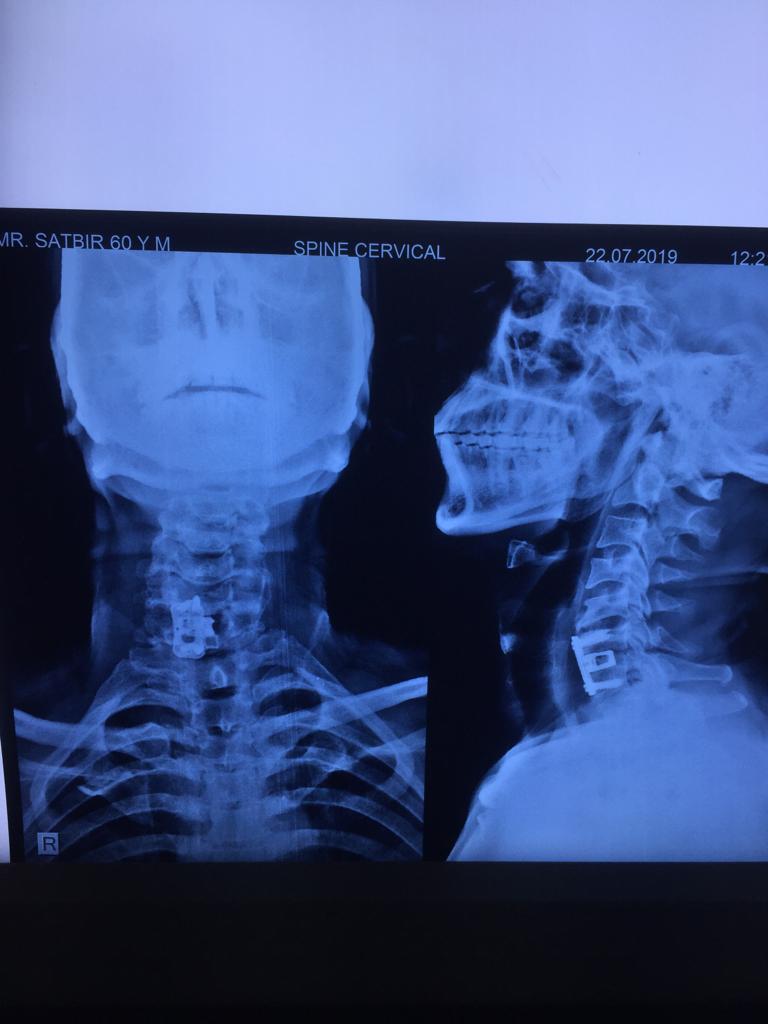

Cases